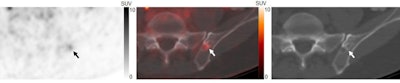

Two nuclear medicine physicians categorized the IBLs on the images as either benign, malignant, or equivocal, noting lesion locations' maximum standard uptake values (SUVmax) for each.

Overall, 98 IBLs were identified in 48 of the 243 patients (19.8%). Of these, 37 were categorized as benign, 42 as malignant, and 19 as equivocal.

Of the benign IBLs, 91.9% showed SUVmax < 5 or exhibited focal uptake without coexisting bone metastases. Conversely, 88.1% of the IBLs deemed malignant demonstrated SUVmax ≥ 5 or were present with coexisting bone metastases.

The study suggests that IBLs are likely malignant in the presence of other bone metastases and that those with SUVmax ≥ 5 at two-hour uptake of F-18 DCFPyL have increased likelihood of malignancy, the authors wrote.